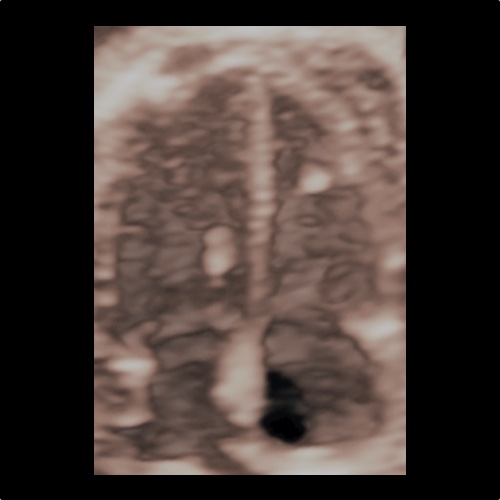

Ecocardiografia fetale 3D